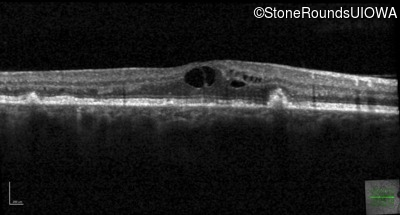

Age at visit: 49 years

This 49 year old man was first told he had a fundus abnormality on a routine eye exam at age 34. Ten years later he noticed some distortion just superior to fixation.

Age at visit: 49 years (Visit 2)

Pattern Dystrophy PRPH2 Gln239Stop CAG>TAG   AD